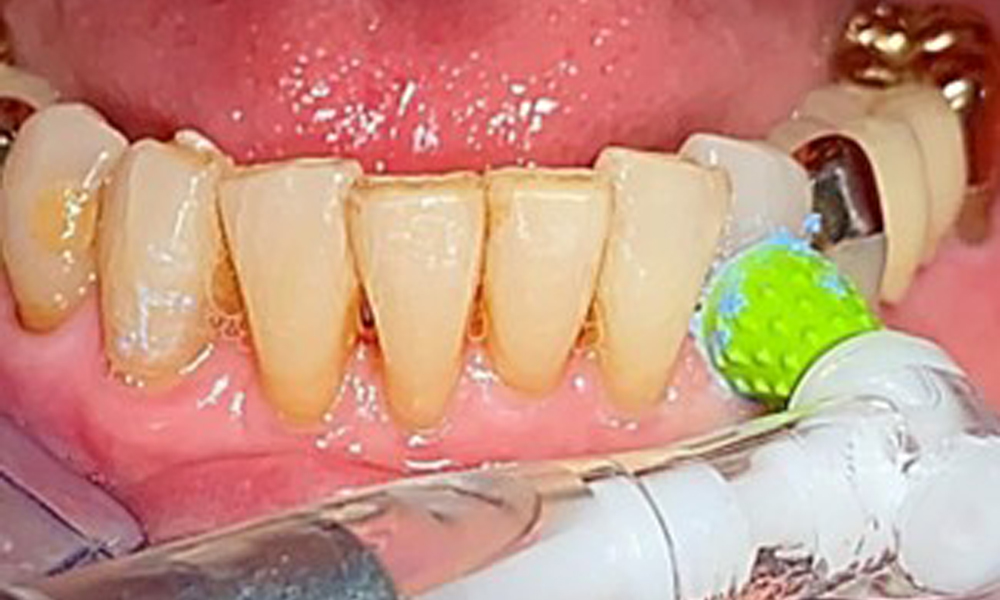

A single-tufted brush is specifically recommended for the telescopic prostheses (Fig. 8) and the patient should be advised on the appropriate interdental brush size (Fig. 9). The patient has been implementing these recommendations for intraoral hygiene at home for many years and was encouraged to continue during the professional preventive dental appointment.

Illustration of a single-tufted brush for home care of the implants and telescopic prostheses.

Fig. 8: Illustration of a single-tufted brush for home care of the implants and telescopic prostheses.